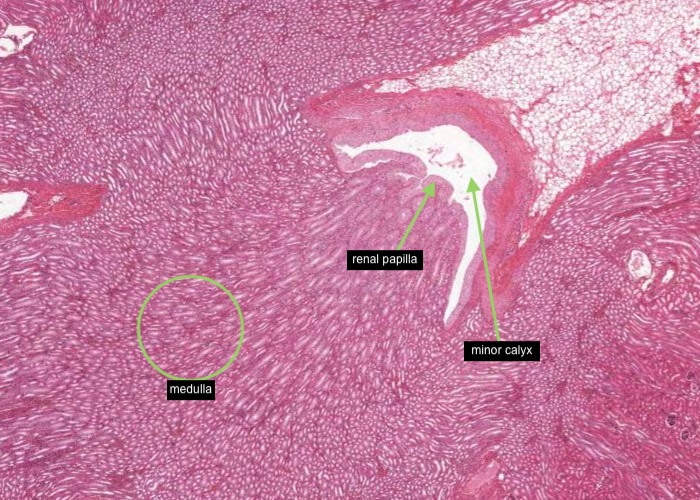

In most stained sections of kidney (including H&E), the medulla is the lighter stained inner region of the kidney. It contains straight tubules and collecting ducts with associated blood capillaries - the vasa recta. These tubules form conical shaped renal pyramids - their base faces the cortex and the apices open into a minor calyx through the tip of each pyramid (renal papilla). Pyramids are separated by extensions of the cortex (renal columns).

A renal pyramid is a conical structure in the medulla formed by the tubules. Humans may have 8-12 pyramids. The base of the pyramid faces the cortex and the apex (papilla) projects into the minor calyx

The renal papilla is the tip of each pyramid. The indented epithelial surface at the tip of the papilla (area cribosa) may represent the merging of collecting ducts to form a papillary duct (duct of Bellini) that empties urine into the minor calyx. The collecting ducts are wider in diameter and will exhibit epithelium with increasing numbers of columnar cells.